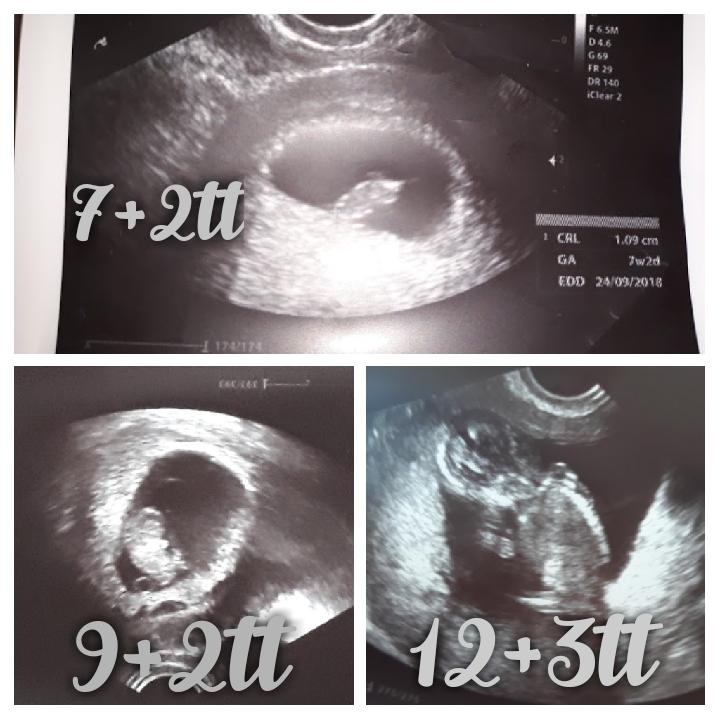

Nieco sa pecie 😍